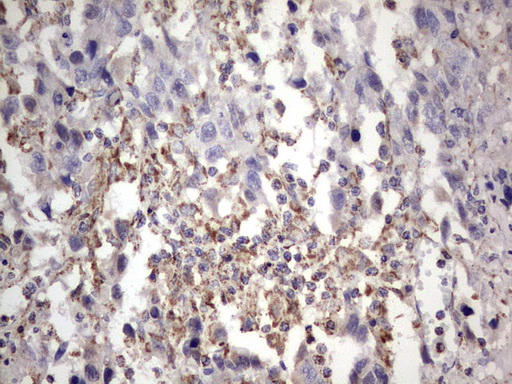

Immunohistochemical staining of paraffin-embedded Adenocarcinoma of Human colon tissue using anti-APC mouse monoclonal antibody. (M00008-2; heat-induced epitope retrieval by 1mM EDTA in 10mM Tris, pH8.5, 120°C for 3min)

Immunohistochemical staining of paraffin-embedded Adenocarcinoma of Human colon tissue using anti-APC mouse monoclonal antibody. (M00008-2; heat-induced epitope retrieval by 1mM EDTA in 10mM Tris, pH8.5, 120°C for 3min)